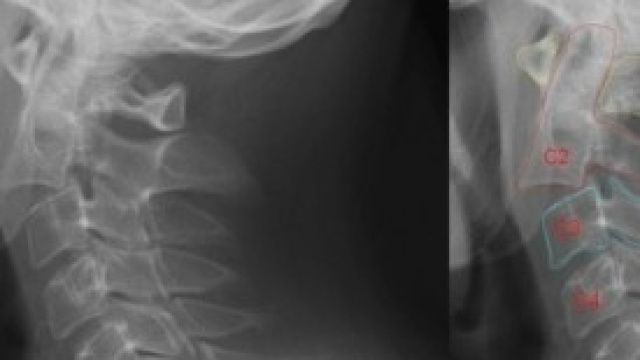

Come abbiamoprecedentemente indicato, le cause della cervicale sono di varia natura: contratturamuscolare, stress e tensioni accumulate oppure cause ben più gravi come loschiacciamento delle vertebre, ernia discale, ernia cervicale e artrosicervicale.

La contrattura muscolare e l'ernia cervicale sono le cause più frequenti cheprovocano gravi disturbi come : fortimal di testa. frequenti capogiri, blocco quasi totale della colonna cervicale oil blocco delle funzioni muscolari del collo.